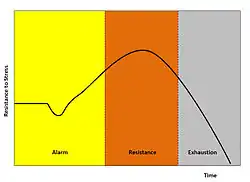

Physiologists define stress as how the body reacts to a stressor - a stimulus, real or imagined. Acute stressors affect an organism in the short term; chronic stressors over the longer term. The general adaptation syndrome (GAS), developed by Hans Selye, is a profile of how organisms respond to stress; GAS is characterized by three phases: a nonspecific alarm mobilization phase, which promotes sympathetic nervous system activity; a resistance phase, during which the organism makes efforts to cope with the threat; and an exhaustion phase, which occurs if the organism fails to overcome the threat and depletes its physiological resources.[56]

Stage 1

Alarm is the first stage, which is divided into two phases: the shock phase and the antishock phase.[57]

- Shock phase: During this phase, the body can endure changes such as hypovolemia, hypoosmolarity, hyponatremia, hypochloremia, hypoglycemia—the stressor effect. This phase resembles Addison's disease. The organism's resistance to the stressor drops temporarily below the normal range and some level of shock (e.g. circulatory shock) may be experienced.

- Antishock phase: When the threat or stressor is identified or realized, the body starts to respond and is in a state of alarm. During this stage, the locus coeruleus and sympathetic nervous system activate the production of catecholamines including adrenaline, engaging the popularly-known fight-or-flight response. Adrenaline temporarily provides increased muscular tonus, increased blood pressure due to peripheral vasoconstriction and tachycardia, and increased glucose in blood. There is also some activation of the HPA axis, producing glucocorticoids (cortisol, aka the S-hormone or stress-hormone).

Stage 2

Resistance is the second stage. During this stage, increased secretion of glucocorticoids intensifies the body's systemic response. Glucocorticoids can increase the concentration of glucose, fat, and amino acid in blood. In high doses, one glucocorticoid, cortisol, begins to act similarly to a mineralocorticoid (aldosterone) and brings the body to a state similar to hyperaldosteronism. If the stressor persists, it becomes necessary to attempt some means of coping with the stress. The body attempts to respond to stressful stimuli, but after prolonged activation, the body's chemical resources will be gradually depleted, leading to the final stage.